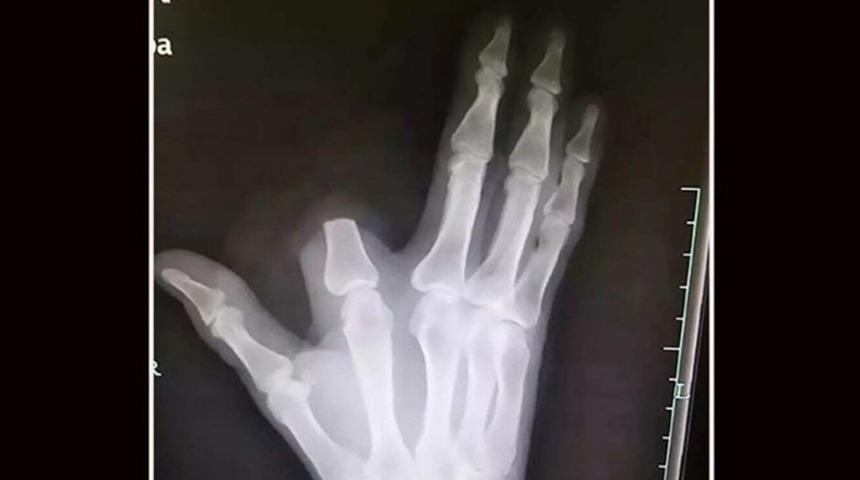

South China Morning Post’un haberine göre Çin'in Zhejiang eyaletinin Shangyu bölgesinden bir çiftçiyi, deinagkistrodon cinsi bir çukur engerek yılan soktu. Yerel inanışa göre bir kişiyi yılan soktuğunda sadece beş adım yürüyebilir. Bu nedenle 60 yaşındaki adam hızlı davrandı, yılanın ısırdığı parmağını kesti ve yarayı sardı. Yaşlı adam bu şekilde 80 km uzaklıktaki hastaneye ulaştı.

Hangzhou Hastanesi’nden doktorlar, yaşlı çiftçiyi Zhang ismi ile duyurdular. Doktorlar, Zhang’ın hastaneye geldiğinde durumunun iyi göründüğünü bildirdi. Yaşlı adam hastaneye ulaştığında solunum problemi, baş ağrısı ya da kötü bir yılan sokmasından beklendiği gibi diş etlerinde kanama gibi herhangi bir semptom göstermiyordu. Hangzhou Hastanesi’nde görevli doktor Yuan Chengda, “Parmağını kesmesi gerekmiyordu. Deinagkistrodon o kadar da zehirli değildir” açıklaması yaptı.

NE YAZIK Kİ PARMAĞI DİKİLEMEDİ

Çinli çiftçi Zhang’a gelince, yaşlı çiftçiye uygun antivenom uygulandı ve yarası temizlendi. Zhang şu an evinde dinleniyor. Ne yazık ki parmağı yerine dikilemedi. Çünkü onu kestiği yerde bırakıp hastaneye gelmişti.